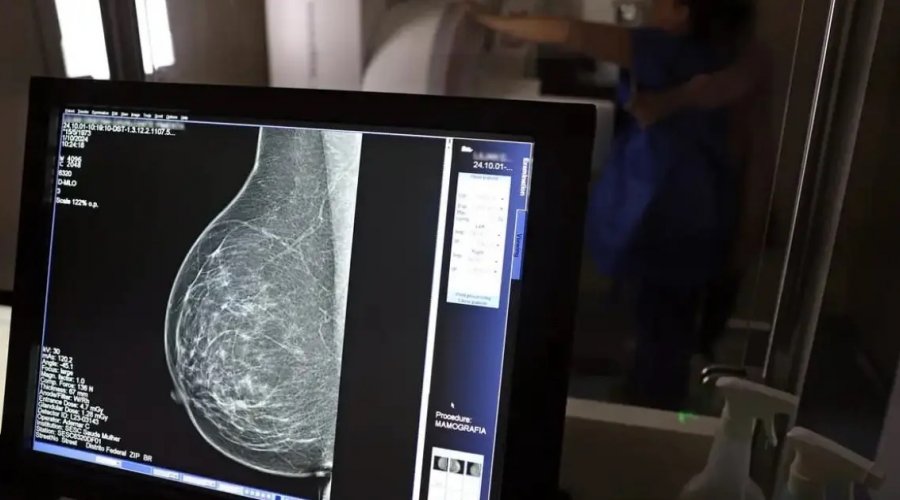

Foto: José Cruz / Agência Brasil

A Superintendência de Estudos Econômicos e Sociais da Bahia (SEI) divulgou o relatório Info Câncer de Mama 2025, que atualiza os dados sobre a doença no estado. O levantamento estima 4,3 mil novos casos em 2024 — uma taxa de 43,8 por 100 mil mulheres. Em Salvador, o número é ainda maior: 64,3 por 100 mil.

O câncer de mama segue como o tipo mais letal entre as mulheres baianas, representando 16% de todas as mortes por neoplasias malignas no estado, com 1,4 mil óbitos registrados em 2024. A taxa de mortalidade foi de 17,5 a cada 100 mil mulheres.

Segundo o economista Jadson Santana, da SEI, o aumento nas taxas reflete mudanças nos padrões de mortalidade no Brasil desde os anos 1960, com o avanço das doenças crônicas e redução das infecciosas.

O relatório também aponta que a doença respondeu por cerca de 5 mil internações no SUS, com taxa de letalidade de 7 a cada mil. A campanha